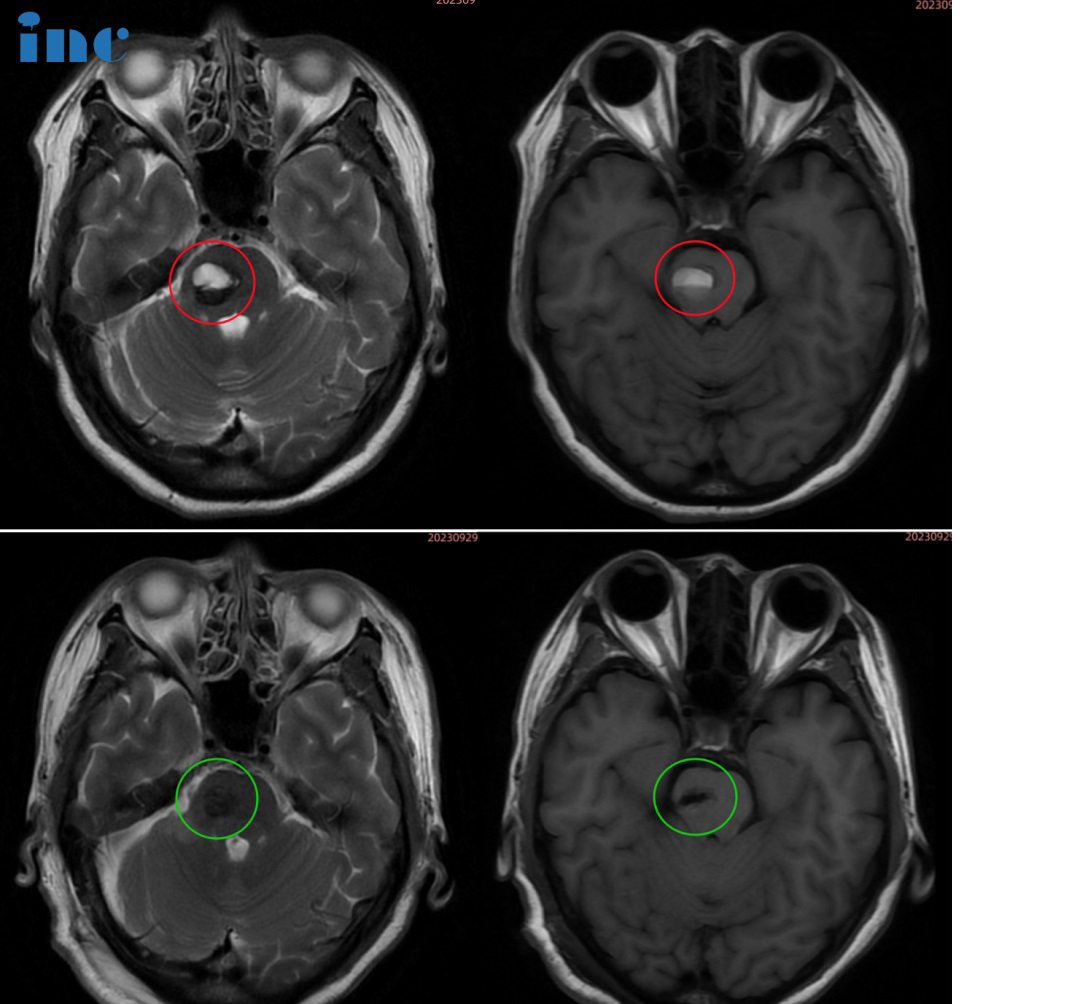

52岁女性•脑干-脑桥海绵状血管瘤

术前情况:2021年8月,由于心脏不舒服,检查发现脑干海绵状血管瘤,尺寸是0.8cm。当时没有症状,医院建议观察随访。2022年1月,复查尺寸1cm,没有症状,继续随访。2023年3月,患者出现阵发性眼肌痉挛,耳朵有时感觉不舒服。再次复查SWI,发现有出血灶(除了眼部,脸部痉挛,没有其他感觉)医生不认为和海绵状血管瘤有关系。2023年6月,再次复查SWI大小1.2cm,继续随访。2023年8月31日,患者出现头晕,急诊完善头颅核磁,提示有新鲜出血灶,尺寸2.0*1.7*1.8cm。眼肌,脸部痉挛稍有加重,依然是阵发性的。耳朵也是有时不舒服,偶尔头晕。脑干海绵状血管瘤出血灶不断变大,症状也在不断加重,保守观察已经无法缓解她的病情,目前解决的办法只有手术。在多方问询之后,她看到了国际脑干颅底手术教授巴教授在国内示范教学手术的信息。

治疗过程:9月28日,在苏州独墅湖医院,巴教授顺利为其顺利全切手术,无任何新发神经功能损伤。

术后情况:术后1天ICU查房,感觉状态良好,四肢活动正常。术后2天查房,可以坐起,面部没有麻木。术后3天查房,已经下地走路,教授检查了双眼运动。术后5天查房,金女士恢复良好,和前来查房的巴教授合影留念。术后一个半月,金女士已经逐渐恢复正常工作和生活。